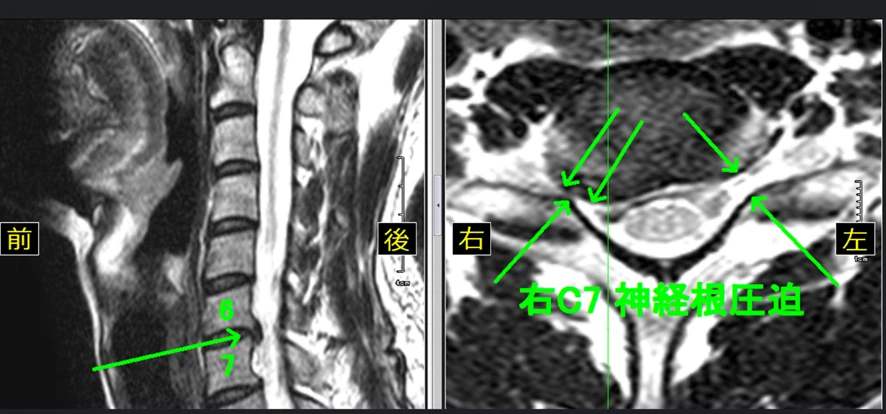

【12級レベルの頚椎のMRI画像】

※頚椎椎間板の大きな膨隆が認められるとともに右神経根の圧迫が認められます。